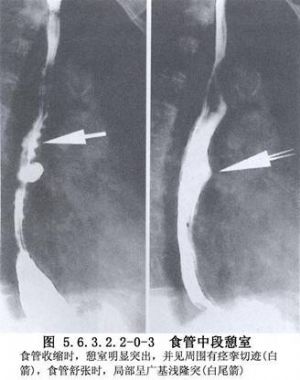

食管中段憩室的诊断主要依靠食管钡餐造影检查和内镜检查。在做钡餐造影检查时,患者取头低脚高位或俯卧位,或取左侧卧位,憩室的位置和轮廓容易显示。必要时做食管CT检查和食管功能测定,以除外其他较严重的疾病。如果出现慢性肺化脓症的症状,则有必要做气管镜检查和肺CT扫描,以明确肺部病变的范围。如怀疑有憩室-支气管瘘,须做支气管碘油造影或气管镜检查;内镜检查有助于发现瘘口。嘱患者口服亚甲蓝或其他染料,若在痰中发现蓝色,即可以确诊(图5.6.3.2.2-0-1~5.6.3.2.2-0-4)。